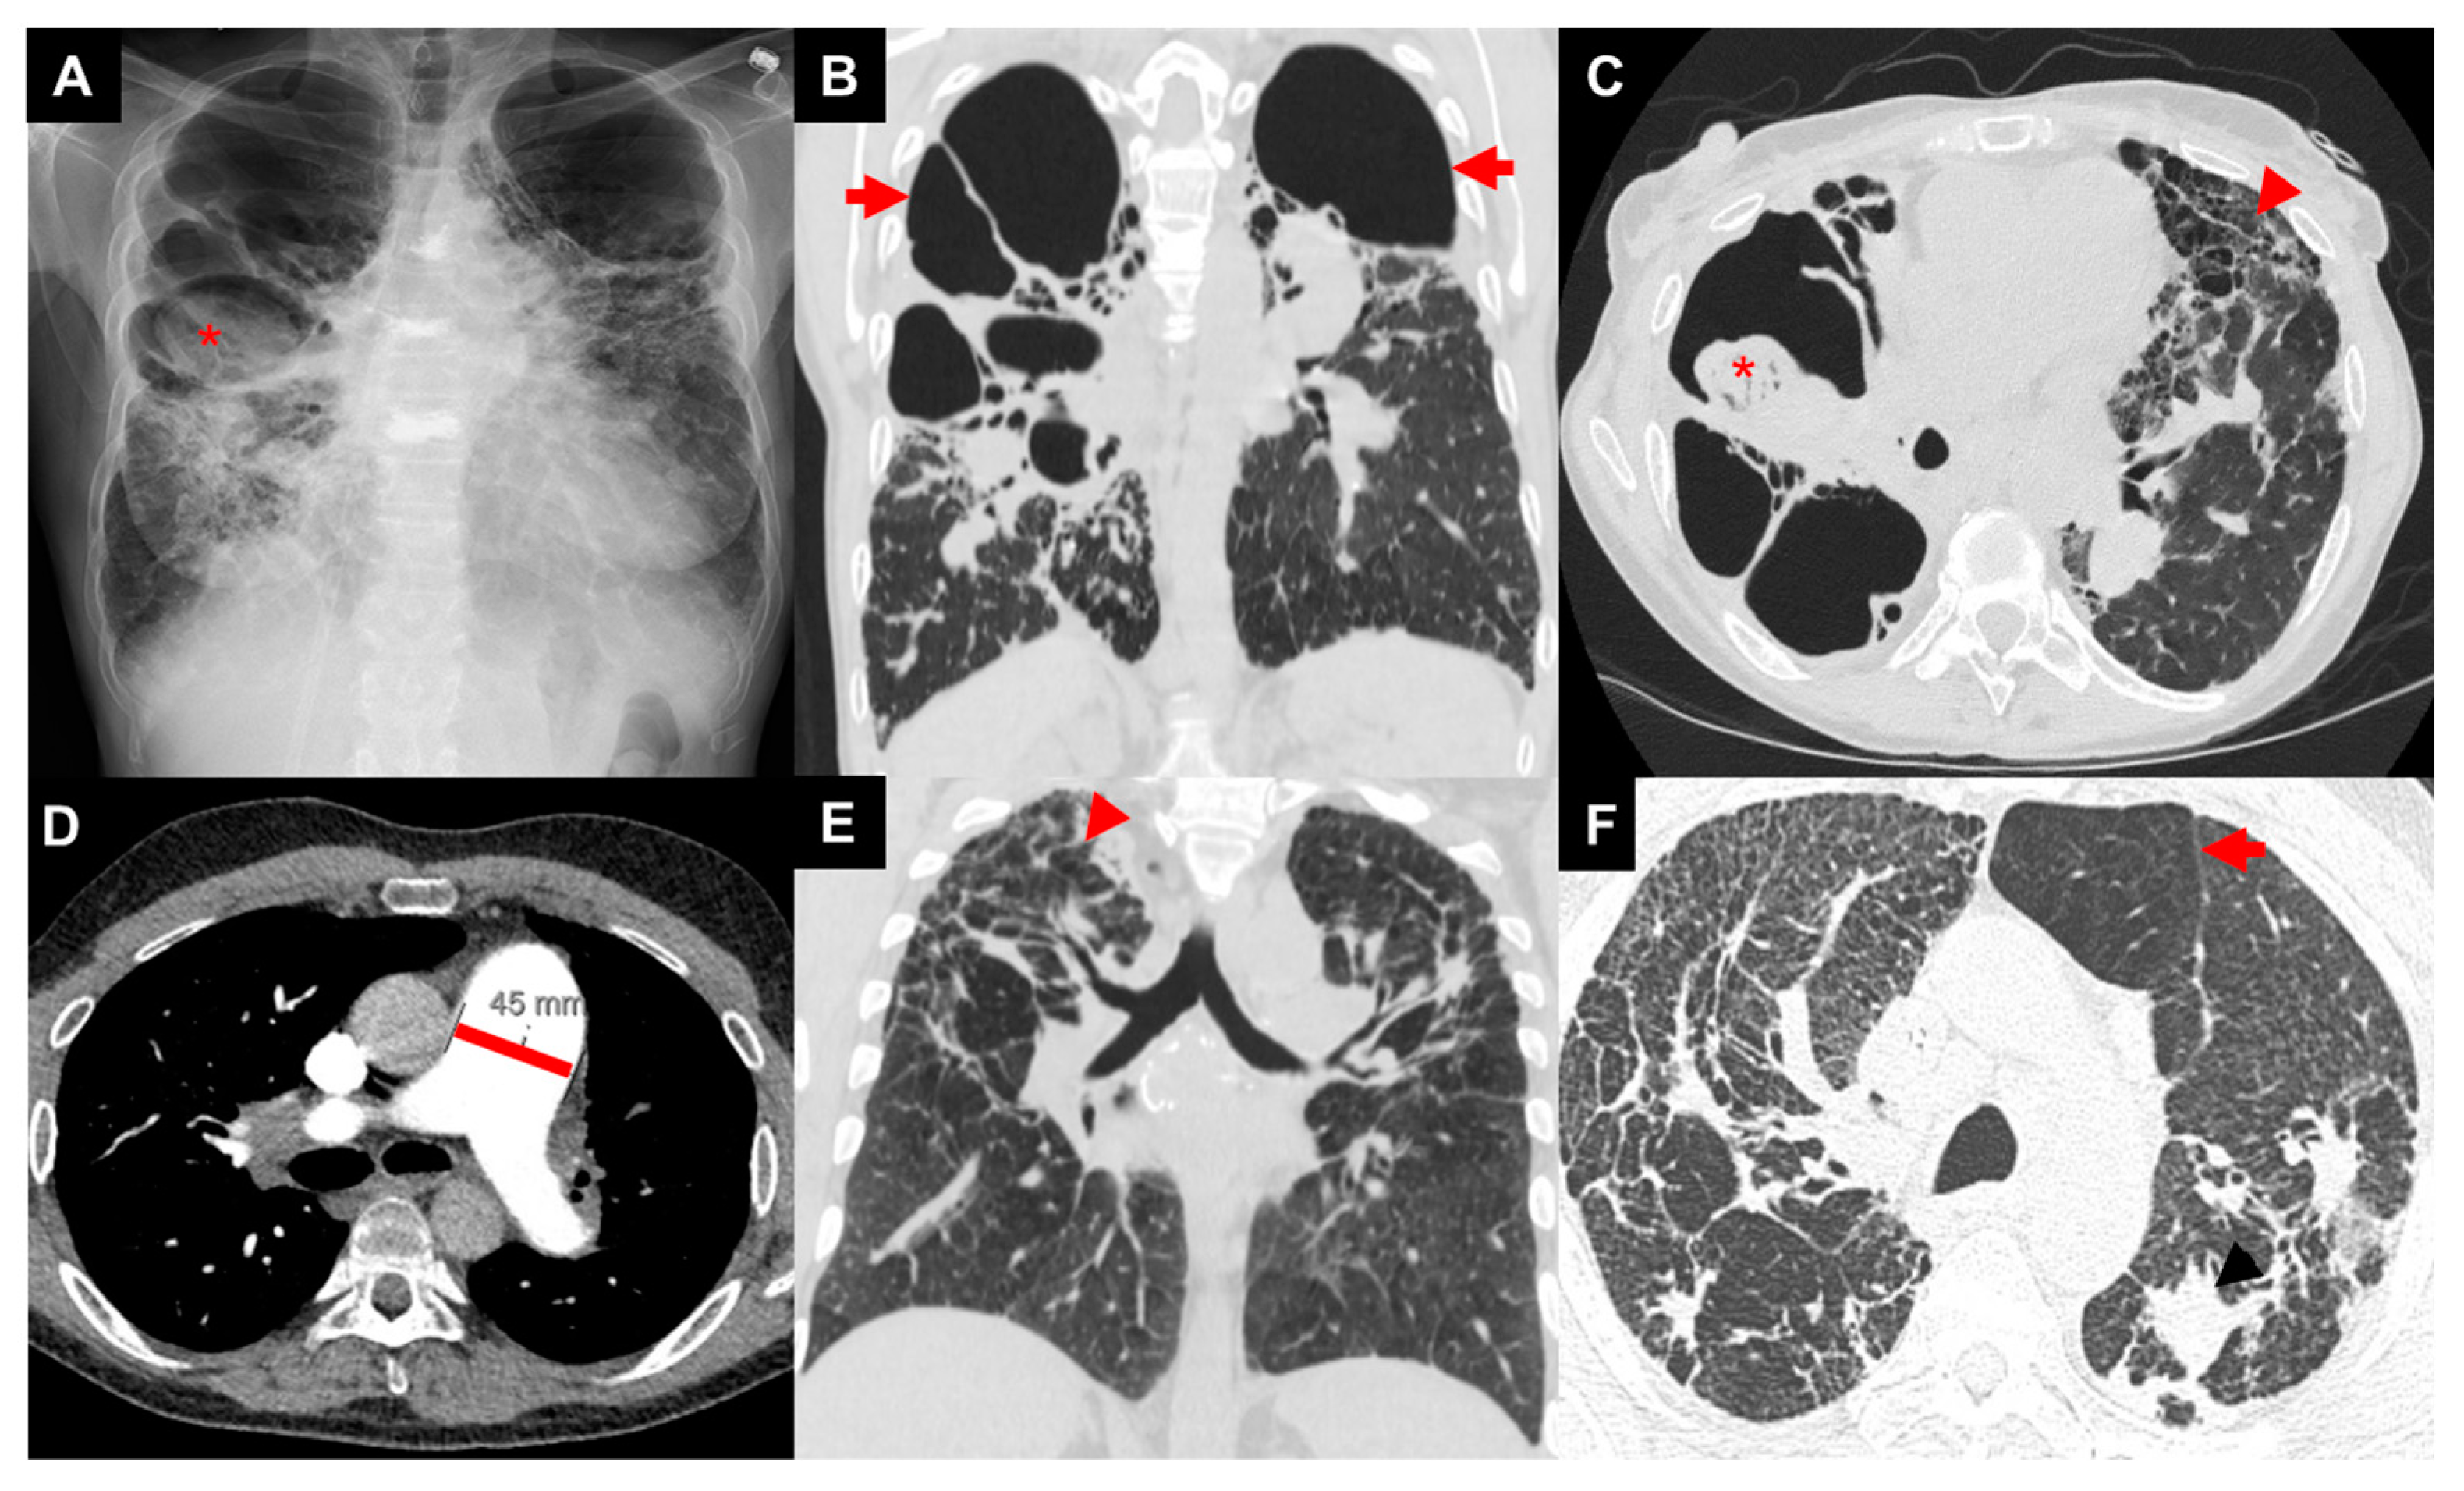

3.1. Imaging

- Abehsera, M.; Valeyre, D.; Grenier, P.; Jaillet, H.; Battesti, J.P.; Brauner, M.W. Sarcoidosis with pulmonary fibrosis: Ct patterns and correlation with pulmonary function. AJR Am. J. Roentgenol. 2000, 174, 1751–1757. [Google Scholar] [CrossRef]

- Criado, E.; Sanchez, M.; Ramirez, J.; Arguis, P.; de Caralt, T.M.; Perea, R.J.; Xaubet, A. Pulmonary sarcoidosis: Typical and atypical manifestations at high-resolution ct with pathologic correlation. Radiographics 2010, 30, 1567–1586. [Google Scholar] [CrossRef]

- Walsh, S.L.; Wells, A.U.; Sverzellati, N.; Keir, G.J.; Calandriello, L.; Antoniou, K.M.; Copley, S.J.; Devaraj, A.; Maher, T.M.; Renzoni, E.; et al. An integrated clinicoradiological staging system for pulmonary sarcoidosis: A case-cohort study. Lancet Respir. Med. 2014, 2, 123–130. [Google Scholar] [CrossRef]

- Nunes, H.; Uzunhan, Y.; Gille, T.; Lamberto, C.; Valeyre, D.; Brillet, P.Y. Imaging of sarcoidosis of the airways and lung parenchyma and correlation with lung function. Eur. Respir. J. 2012, 40, 750–765. [Google Scholar] [CrossRef] [PubMed]